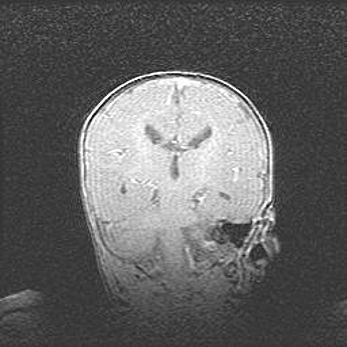

Открытая гидроцефалия.

Возраст: 6 месяцев 15 дней

Вес: 6200 г

Пол: женский

Окружность головы: 41 см

Срок гестации: 38 недель

Гидроцефалия головного мозга у новорожденных – это скопление избыточного количества цереброспинальной жидкости в головном мозге. Ее избыточное скопление в мозге приводит к патологическому расширению желудочков мозга (четырех полостей, расположенных в глубине белого вещества мозга, заполненных цереброспинальной жидкостью и связанных узкими проходами).

Открытый тип гидроцефалии (сообщающаяся) наблюдается тогда, когда нарушен механизм всасывания ликвора в системный кровоток. При этом типе причиной заболевания чаще всего является перенесенные ранее инфекции (например: менингит),  либо же наличие крови в субарахноидальном пространстве.